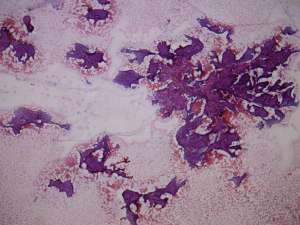

Cytological diagnosis: papillary cancer.

Histopathology: papillary cancer based on the nodule in the right lobe and benign follicular adenoma based on the nodule in the left lobe.